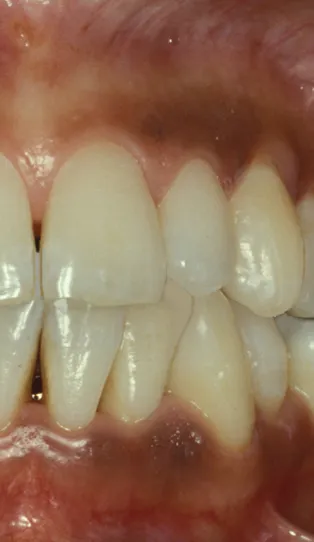

What are Smoker’s Gums?

Smoker’s melanosis is the darkening of the gums, lips, and soft palate of the mouth due to smoking. It affects about 5% to 22% of cigarette and pipe smokers.

This benign (noncancerous) condition most often affects the gum tissue around the upper and lower front teeth. The more a person smokes the darker the discoloration.

Smoker’s melanosis has no treatment. However, the gums usually return to their normal color within 6 to 36 months after people with this condition quit smoking.

Image source: Wikipedia Commons

Healthy Gums vs. Smoker’s Gums

Healthy gums are firm and pink in color. Any redness, swelling, or bleeding may be warning signs of gum disease. These signs can be masked in a smoker’s gums.

Even though smokers’ gums aren’t healthy, they’re less likely to show redness and bleeding. This is because the nicotine in tobacco reduces circulation to the tiny blood vessels in the gums.